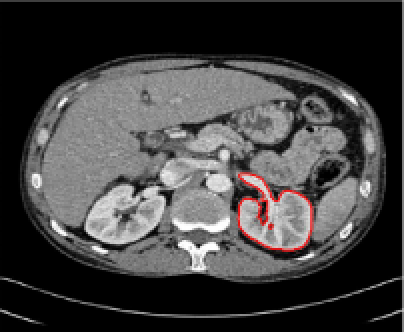

In Figure 2, each column shows an example for each of the problems listed above. We now propose solutions to each of these problems.

Refer to caption

Figure 2: Examples of images showing the problems discussed and the resulting geodesic distance maps. Column 111 shows the lack of robustness to noise, column 222 shows that outside the patient we have unreasonably low distance penalty, column 333 shows how the blurred edge under the aorta leads to the distance term being very low throughout the heart.

Problem 2: Objects far from \mathcal{M} with low penalty.

In Figure 2 column 2 we see that the geodesic distance to the outside of the patient is lower than to their ribs. This is due to the fact that the region outside the body is homogeneous and there is almost zero distance penalty in this region. Similarly for Figure 3 column 444, the distances from the marker set to many surrounding objects is low, even though their Euclidean distance from the marker set is high. We wish to have the Euclidean distance 𝒟E(x,y)subscript𝒟𝐸𝑥𝑦\mathcal{D}_{E}(x,y) incorporated somehow. Our solution is to modify the term f1(x,y)subscript𝑓1𝑥𝑦{f}_{1}(x,y) from (16) to